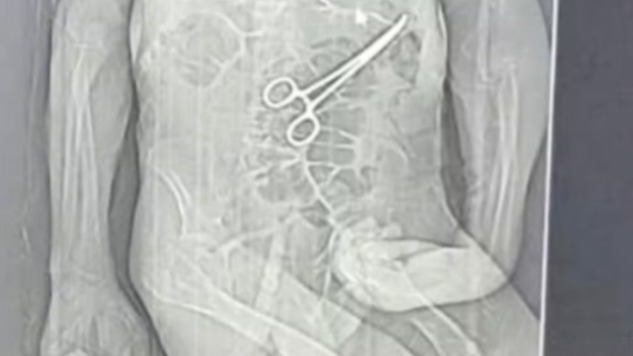

Tomografia mostrou pinça cirúrgica dentro do corpo do paciente após cirurgia em João Pinheiro — Foto: Rádio Nova FM/Reprodução

Segundo o advogado da família do idoso, Iuri Evangelista Furtado, as medidas legais começaram a ser adotadas depois que um exame de tomografia, divulgado por uma rádio local, chegou ao conhecimento de parentes. A imagem indicaria a presença do instrumento cirúrgico no corpo do paciente.